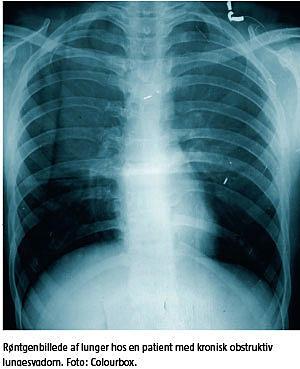

På verdensplan er kronisk obstruktiv lungesygdom (KOL) den femtehyppigste dødsårsag, og WHO forudser, at dette tal vil stige, således at KOL forventes at blive den fjerdehyppigste dødsårsag i 2030 [1]. Akutte eksacerbationer øger faldet i lungekapaciteten ud over den akutte periode og forringer livskvaliteten hos patienterne [2]. Den vigtigste risikofaktor for udvikling af sygdommen er tobaksrygning.